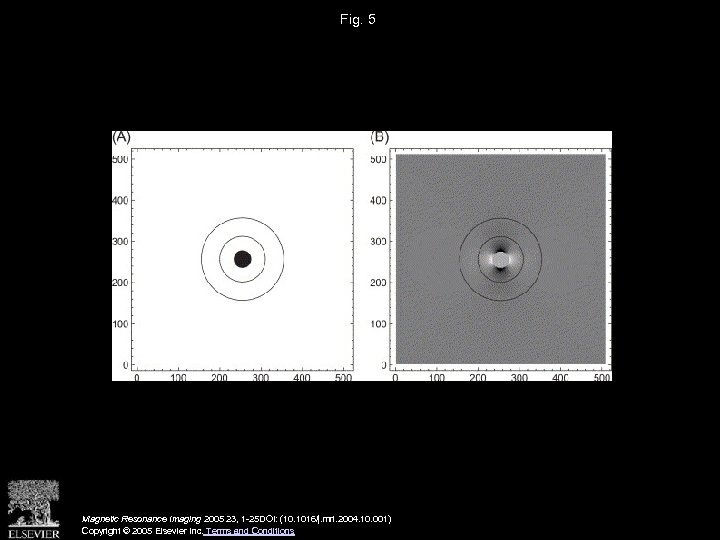

Fig. 5 Magnetic Resonance Imaging 2005 23, 1 -25 DOI: (10. 1016/j. mri. 2004. 10. 001) Copyright © 2005 Elsevier Inc. Terms and Conditions